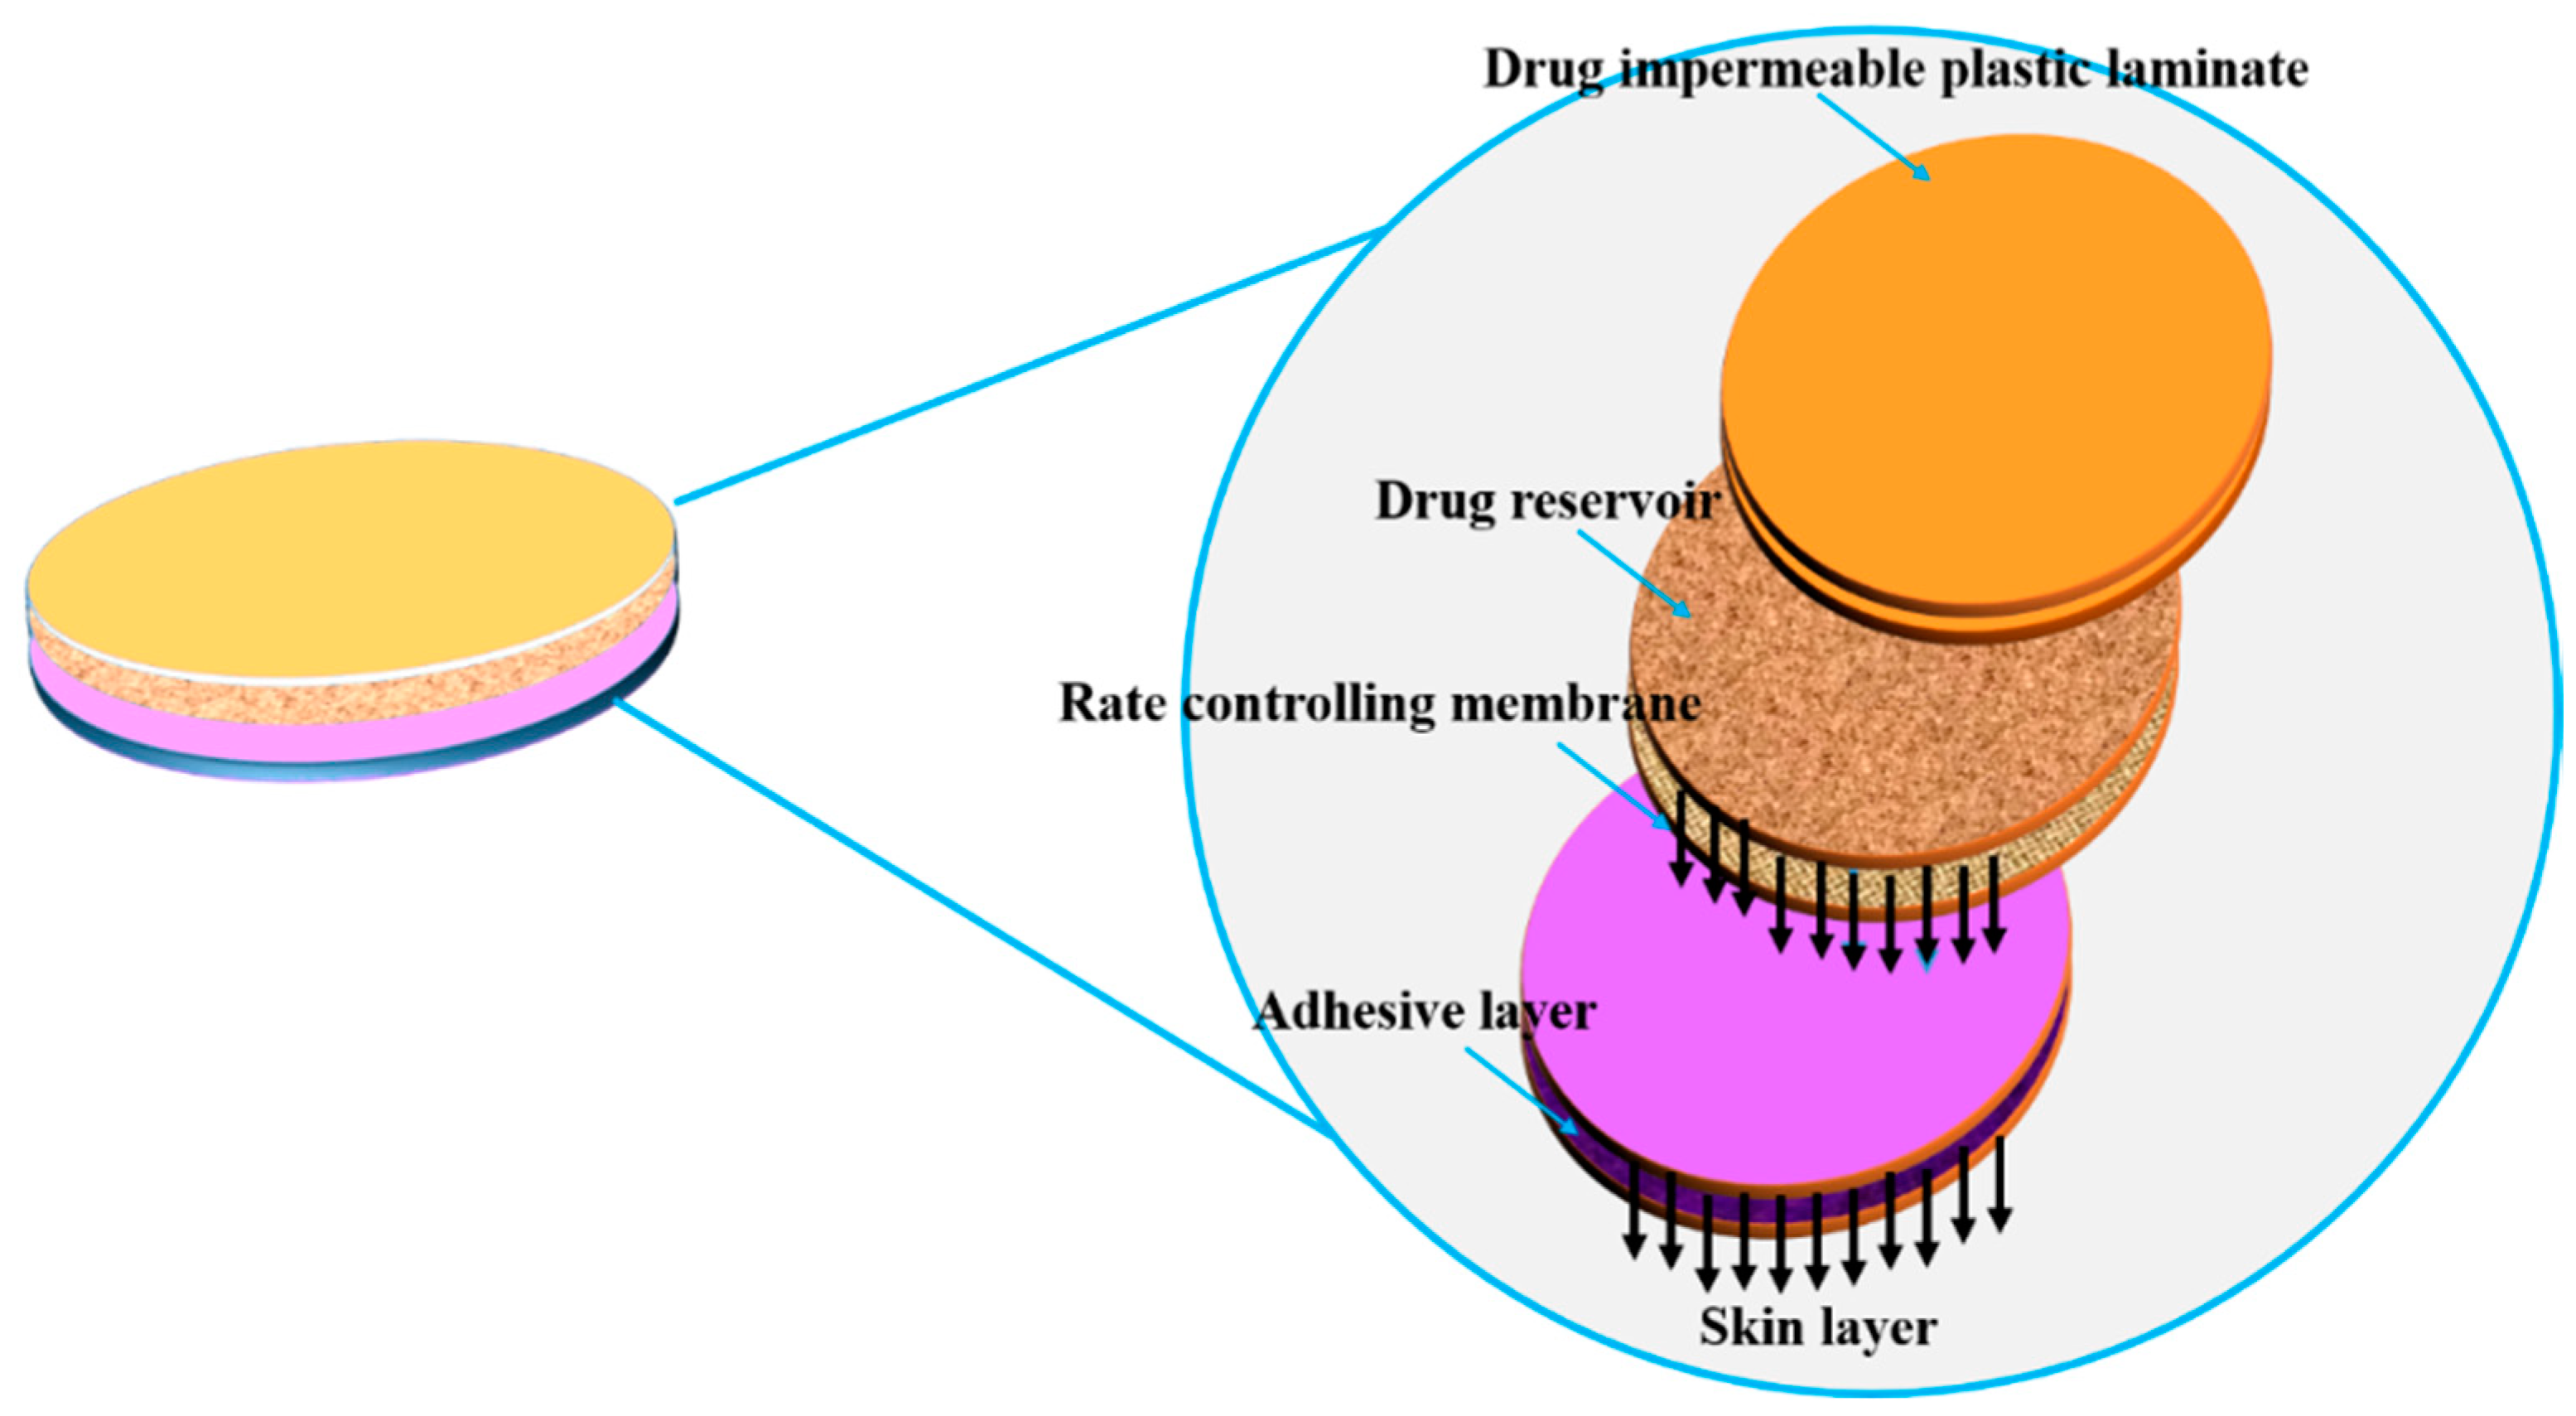

5.2.2. Transdermal Systems

- Yang, W.W.; Pierstorff, E. Reservoir-based polymer drug delivery systems. J. Lab. Autom. 2012, 17, 50–58. [Google Scholar] [CrossRef]